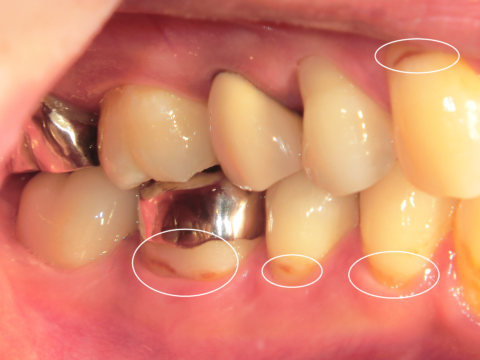

お口の中でこのような根元になっている所はありませんか?

それは根面う蝕の始まりかもしれません・・・

根面う蝕は、歯周病治療との関連性が強く、歯周病などで歯の根面が露出した部分に発生する虫歯です。